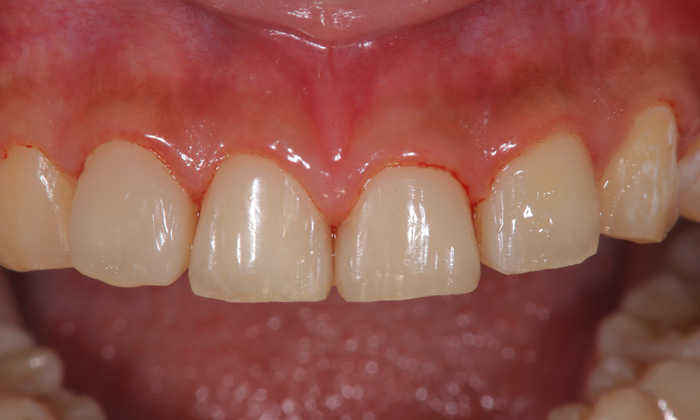

治療後

患者さまはまだ10代ということもあり、神経を取ってしまうのはいかがなものかと先に通っていた歯科医院の先生も考え、当院を紹介してくれたそうです。そのため、神経を残すことを最優先にする治療を行いました。

まずは悪くなっている歯質のみを削りました。写真からも分かるように、残せた健康な歯はたったこれだけしかありません。その後、直接法コンポジットレジン修復という、歯に直接素材を接着する方法を行いました。歯のすき間や表面を埋め、機能性や見た目を整えました。